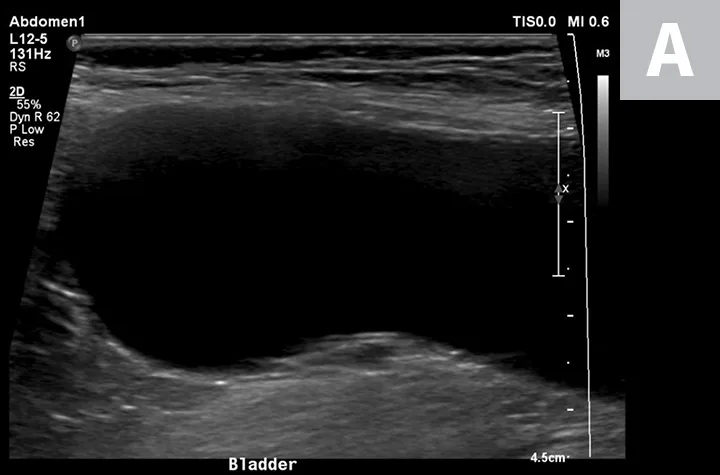

Cystocentesis is often performed with ultrasonographic guidance, although this is not required (ie, blind cystocentesis). Using ultrasonography can help direct visualization of the needle in the urinary bladder lumen, avoiding iatrogenic damage of surrounding structures (Figure 1). The relative size of the bladder, echogenicity of its contents, and any obvious structural abnormalities can also be observed. A primary advantage of blind cystocentesis is that it does not require special equipment. Cystocentesis can be challenging to perform in patients that have abdominal effusion and should be performed with ultrasonographic guidance in such cases.

FIGURE 1

Ultrasonographic image showing the cranial aspect of the urinary bladder (A), identified just before ultrasound-guided cystocentesis. It is important to adjust the depth of the image so that the urinary bladder is focused and to consider the depth of the urinary bladder using a machine scale that should be present on the ultrasound screen; in smaller patients the needle may only be partially inserted and not reach the hub (B; arrow).